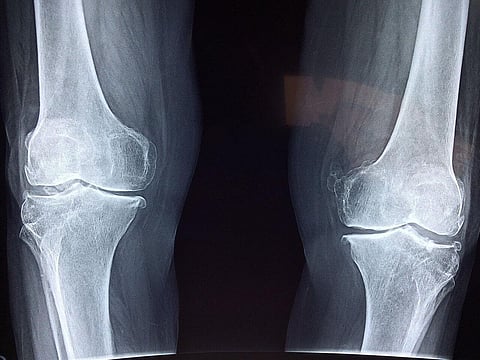

In a major global study, researchers have found that the cases of musculoskeletal disorders — which affect muscles, tendons, ligaments, bones, and joints, are rising rapidly across the globe.

Musculoskeletal disorders can severely affect individuals' physical and mental health, and they're especially prevalent among aging adults, the findings, published in the journal Arthritis & Rheumatology, reported.

Musculoskeletal disorders included rheumatoid arthritis, osteoarthritis, low back pain, neck pain, gout, and related conditions.